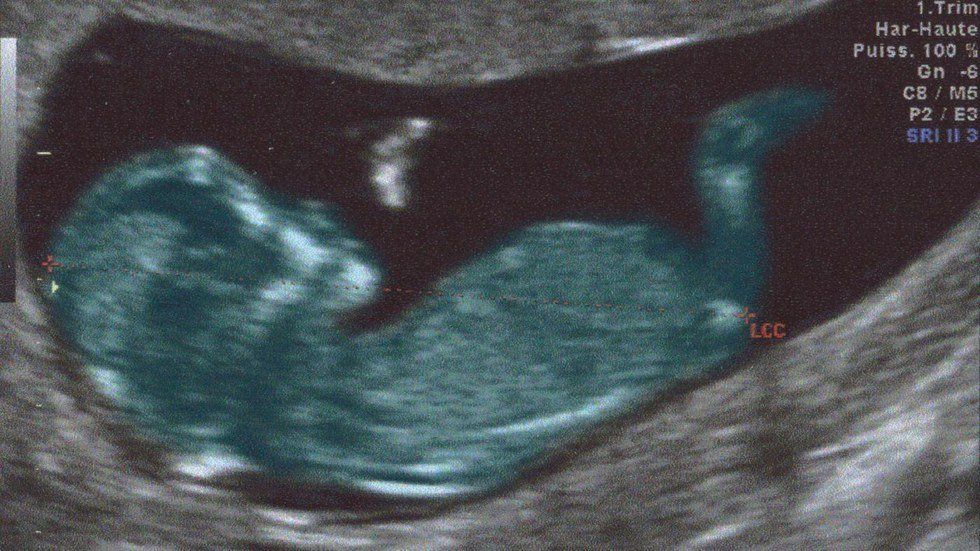

First of all, the pelvic inlet (the opening in the middle) is much smaller than you’d expect. In fact, I sat there for a minute and realized that this was so unrealistically small for a five or seven pound baby to emerge from. I have very small hands, and if I put my index fingers and thumbs together to form a circle that is about as big as a pelvic brim usually is. Our professor told us to examine the bones in detail in our table groups and observe any abnormalities we saw. There weren’t any abnormalities that we could see, and we went through the regular motions of figuring out the age of the woman based on the bone features. I took the pelvis and turned it over and for the first time saw something strange. I raised my hand.

Apparently, about 60 percent of childbirths will cause a hairline fracture on your pelvis. Sometimes it’s only the Symphysis pubis, which is a connective piece that holds the front of the pubis together. However, sometimes the iliac crest, the pieces that attach to your sacrum, can form hairline fractures that can grow larger with each child you have. Since fractures heal by forming calluses, you can often tell how many children a deceased woman has had by looking at the fracture markings on her pelvic region.